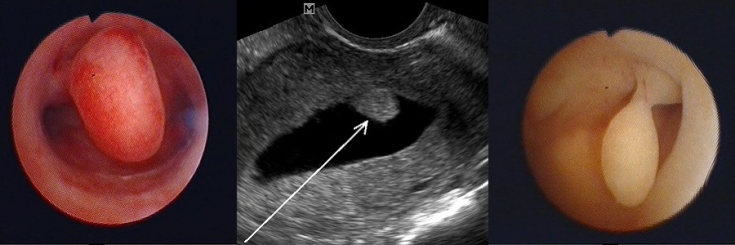

Carried out in the presence of a large single pedunculated polyp. Then it is "twisted", and the remaining wound surface is cauterized with electric current or liquid nitrogen. These manipulations prevent, although not always, the formation of new pathological formations. The operation is quick, however, it is performed under general anesthesia.2. Hysteroscopy

– removal of a polyp using an endoscopic hysteroscope, which is inserted through the cervix into the uterine cavity.3. Curettage.